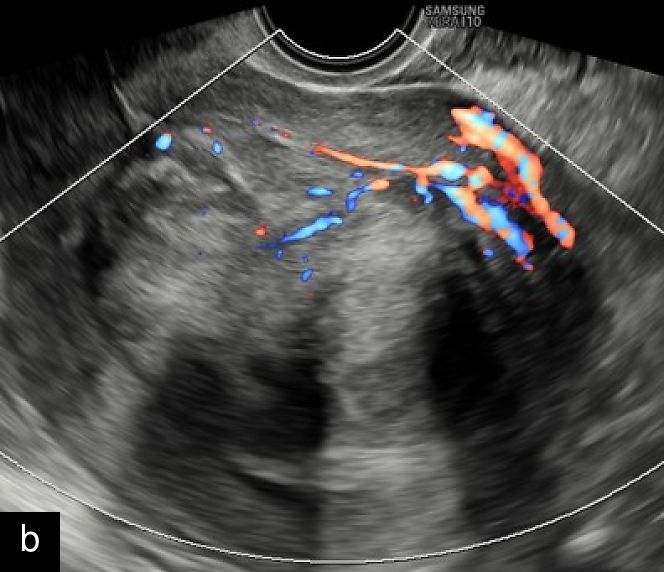

2

Transvaginal ultrasound images with color Doppler of uterine sarcoma, demonstrating heterogeneous echotexture and irregular margins. The Doppler assessment reveals variable vascularization patterns, ranging from moderate (a–b) to extensive (c) intralesional blood flow. Images (b) and (c) show the 'cooked appearance' of solid tissue, a sonographic feature defined by the lack of structure of the solid component and the absence of acoustic shadowing.